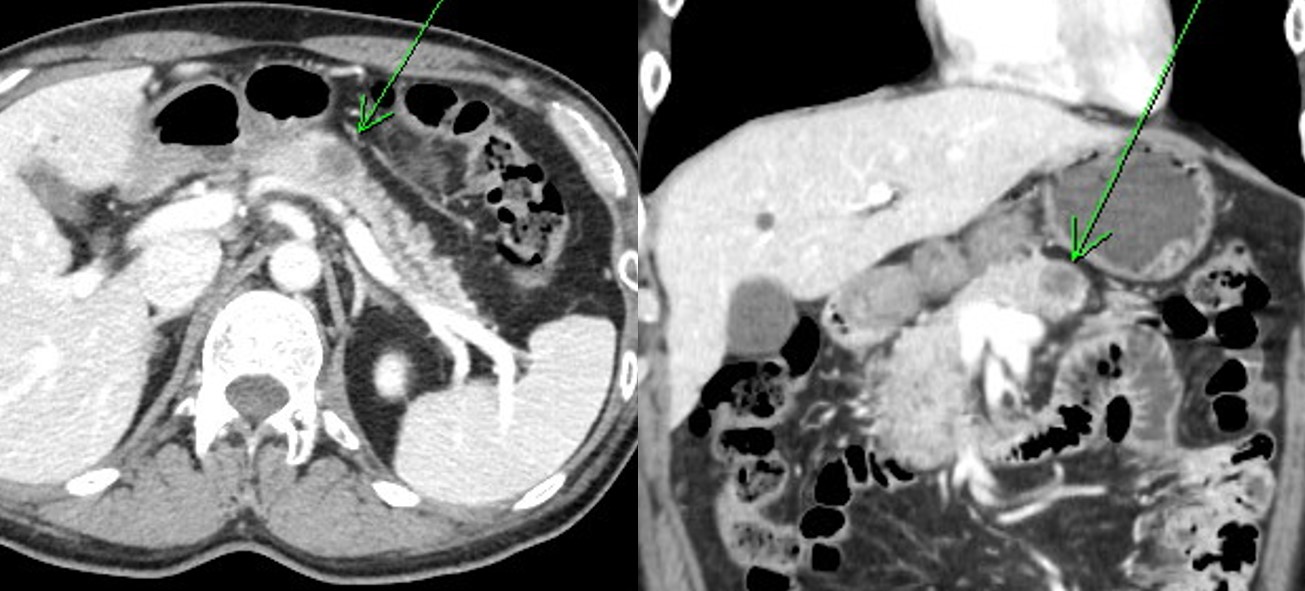

(3) À§ SMT·Î ÀǷڵǾúÀ¸³ª CT¿¡¼­ ½ÅÀå¾Ï ¹ß°ß

Àú´Â À§ EUS¸¦ º°·Î ÁÁ¾ÆÇÏÁö ¾Ê½À´Ï´Ù. ´ëºÎºÐ CT·Î Æò°¡Çϰí ÀÖ½À´Ï´Ù. ±×·± ¿ÍÁß¿¡ ¸¹Àº ÁúȯÀÌ ¹ß°ßµË´Ï´Ù. CT¸¦ »ç¶ûÇÏÁö ¾ÊÀ» ¼ö ¾ø½À´Ï´Ù.

2018³â ³²ÀÚ 60¼¼¿¡¼­ ¹ß°ßµÈ ½ÅÀå¾Ï. SMTµµ ¹«Áõ»óÀÌ°í ½ÅÀå¾Ïµµ ¹«Áõ»óÀÌ´Ï ±×³É ¸ðµç °ÍÀÌ ¿ì¿¬È÷ ¹ß°ßµÈ ¼ÀÀÔ´Ï´Ù. ô¸ú¹ÀÔ´Ï´Ù. Á¶±Ý °úÀåÇϸé ÀÌ·¸½À´Ï´Ù. CT¸¦ Çϸé ô¸ú¹À» ¸¸³­´Ù. EUS¸¦ Çϸé ô¸ú¹À» ¸¸³ªÁö ¸øÇÑ´Ù.

(5) À§ SMT¿¡ ´ëÇÑ ÃßÀû CT¿¡¼­ ¹ß°ßµÈ ÃéÀå¾Ï (2020, F/60)

Àú´Â CT¸¦ »ç¶ûÇÕ´Ï´Ù. EUS¸¦ ±×´ÙÁö ½Å·ÚÇÏÁö ¾Ê½À´Ï´Ù. ÀÌ·± Áõ·Ê¸¦ ¹ß°ßÇϸé CT¸¦ ´õ¿í ¦»ç¶ûÇÏ°Ô µË´Ï´Ù. »ç¶ûÇØ¿ä. CT^^